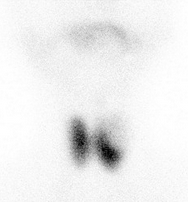

24、多项选择题

患者,男,67岁,乳糜尿1年,35岁以前居住在农村。行Tc-DX动态显像,第4分时的影像如图,描述正确的是()

A.乳糜尿

B.提示左肾肾盏处小淋巴管破裂

C.正常的腹膜后淋巴系统影像

D.注射示踪剂部位应当在双侧1、2趾蹼之间

E.右侧阴囊乳糜样囊肿